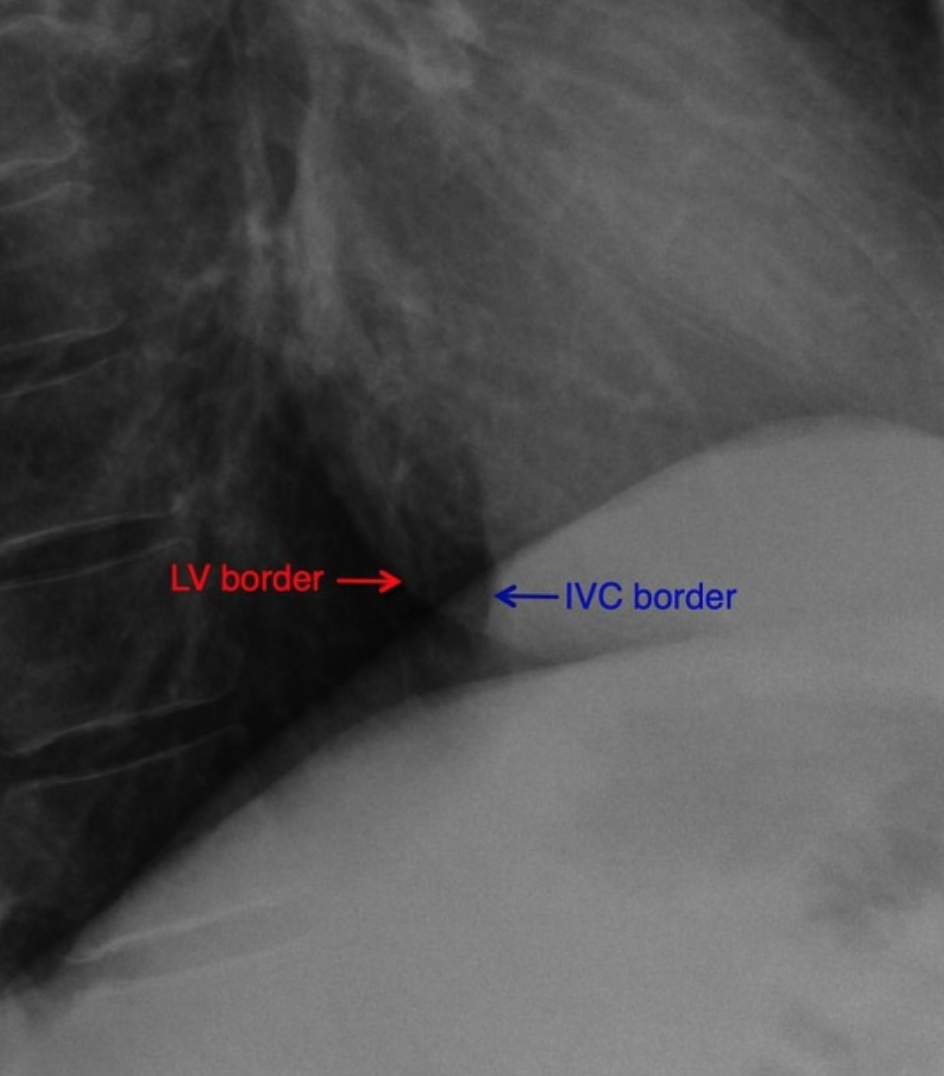

Hoffman-Rigler Sign

• Seen in LV hypertrophy

• Only seen on lateral radiograph and measured 2 cm above the intersection of IVC and diaphragm

• Distance between the LV border and posterior border of IVC is >2.8cm